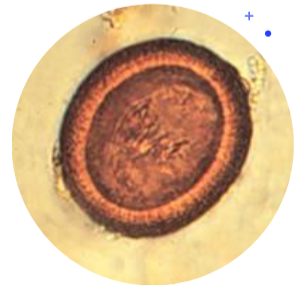

taenia sp eggs

30 x 45 um

Thick, smooth striated shell

Oncosphere has 6 hooks

May not always be visible

Immature larvae

Must find adults to speciate